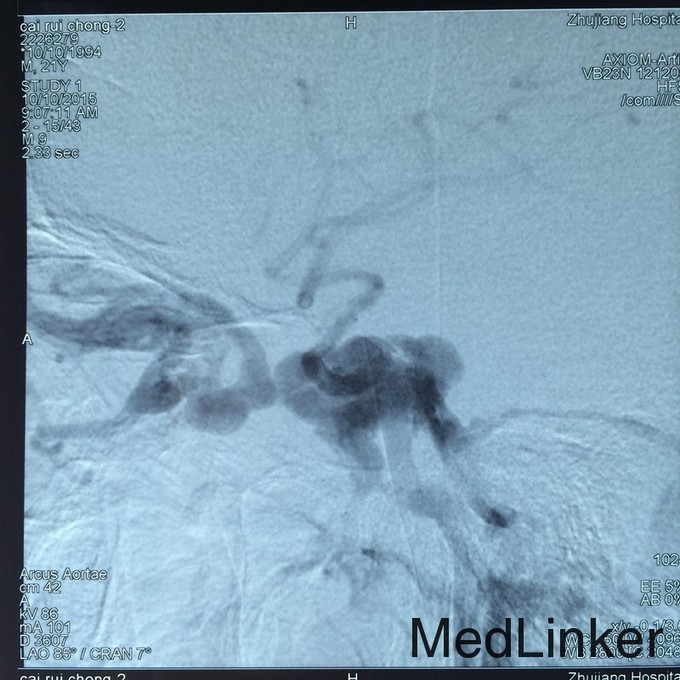

诊断:外伤性颈动脉海绵窦瘘 治疗:在静脉全麻下行头颅DSA提示右侧颈动脉海绵窦瘘,予可脱性球囊将瘘口闭塞。

随访:术后患者症状明显缓解并出院 讨论:该患者为典型的外伤性CCF,颈动脉海绵窦瘘是指海绵窦段的颈内动脉本身或其在海绵窦内的分支破裂,与海绵窦之间形成异常的动静脉沟通,少数颈动脉海绵窦瘘由颈外动脉供血,特称颈外动脉海绵窦瘘。75%以上的为外伤引起,称为外伤性CCF,其余无外伤史者,称为自发性海绵窦瘘。最常见的症状是搏动性突眼和球结膜充血、水肿。首选介入神经放射治疗,经导管将气囊或弹簧圈等栓塞材料放置在痿口处,封闭瘘口,可消除头颅杂音,使眼球回纳,恢复眼球运动。对复发者可再次治疗。